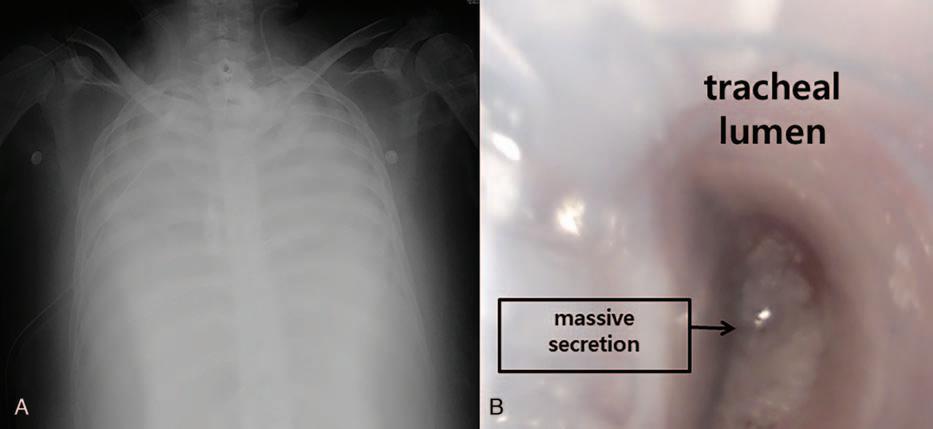

in1second/forcedvitalcapacity,95%;anddiffusingcapacity ofcarbonmonoxide,8.3L/mmHg/min(28%).Veno-venous ECMO,tracheostomy,andmechanicalventilationwere appliedtothepatientfor39dayspreoperativelyasabridge forlungtransplantation.Preoperativechestradiography showedseverediffuselungconsolidations(Fig.1A).Preoperativecardiacechocardiographyshowedreducedrightventricle systolicfunction,mildpulmonaryhypertension(rightventricularsystolicpressure47mmHg),D-shapedleftventriclewith slightlydecreasedleftventriclesystolicfunction(ejection fraction56%).

Theanesthesiawasinducedwithmidazolam3.0mg, sufentanil50 mg,androcuronium50mg.Initially,a35Fr left-sidedDLT(Shiley,Covidien,Mans fi eld,MA)wasinserted viaoralrouteforlungisolationandblindlyplacedat28.5cm depthatthelevelofupperincisorofthepatientaccordingtothe height-basedblindpositioningofDLT.[5] However,bothlungs wereunabletoventilate,andthecon firmationforthe positioningofDLTwithFOB(FIVE4.0,KarlStorz,Tuttlingen, Germany)wasimpossibleduetomassivepulmonarysecretion (Fig.1B).Despitetheefforttosuckoutthepulmonarysecretion withthesuctioncatheterandFOB,anyanatomicstructuresof tracheobronchialtreewereinvisible.Wedecidedtouseanew DLT(ANKOR,InsungMed,Wonju,SouthKorea)ofleft-sided 35Fr(Fig.2A).Afterthecarinalcuffofthetubepassedthrough thevocalcordofthepatient,thetubewasturnedtoleftside,and carinalcuffwasinfl atedwith6mLofair(Fig.2B).Thetubewas advancedfurthertowardleftmainbronchus,anditstoppedat 26.0cmofdepthatthelevelofupperincisorofthepatient.After thede fl ationofthecarinalcuff,thetrachealcuffandthe bronchialcuffofthetubewereinfl atedwith5and2mLofair, respectively(Fig.2C).Afterthecompletionofrightlunggraft, bronchoscopic findingshowedthatthetubewasproperly positionedatthetracheobronchialtreeofthepatientshowing theuppermarginofthebronchialcuffwasslightlyseenat betweenthecarinaandtheleftmainbronchialori ficewithout theobstructionofthetracheallumen(Fig.2D). [6] Surgeons indicatedthattheuseofthenewDLTprovidedexcellent operatingconditionsduringbothlunggrafts.Theoperation timewas10hoursand50minutesunderveno-arterialECMO. ThepatientwastransferredtointensivecareunitwithvenovenousECMO.ECMOwasappliedforpostoperativeday

Figure1. Perioperativeimagesofthepatient.A,Preoperativechestx-ray,showingseverediffuselungconsodiation.B,Bronchoscopic finding,showingmassive pulmonarysecretionwithintheconventionaldouble-lumenendobronchialtube.